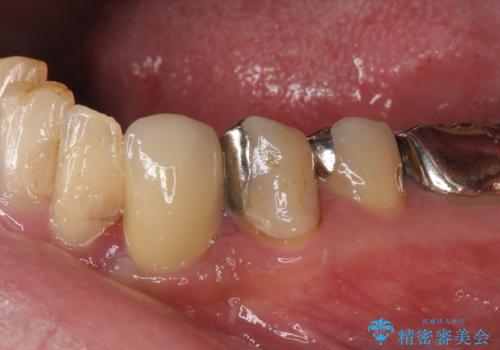

当該歯である犬歯は歯根が長く、安易に抜歯することはおすすめできないため、まずは部分矯正により歯根を引っ張り出し、その後歯周外科処置により歯槽骨や歯肉の状態を整え、最終的にはオールセラミッククラウンにて補綴治療を行うこととしました。

矯正治療中は汚れが溜まりやすく、歯肉からの出血が続きましたが、最終的には歯を保存して安定した状態で補綴治療を行うことができました。